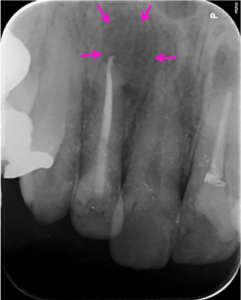

左図のレントゲン写真では右上2番の根の先に炎症があり大きく骨が溶けている部分があります(矢印部) 。

根の治療6か月後のレントゲン写真です。矢印の骨の溶けている部分の大きさが小さく、境界も不明瞭になり、回復してきています。

根の治療1年後のレントゲン写真です。矢印の骨の溶けていた部分は周囲との境界がなくなり、溶けている部分がわからなくなりました。歯の根の周りに一層の骨との境界のライン(歯と骨をつなぐ歯根膜という組織がある部分です)が回復し、歯の周囲組織の本来の姿を取り戻し、完全な回復が見られます。